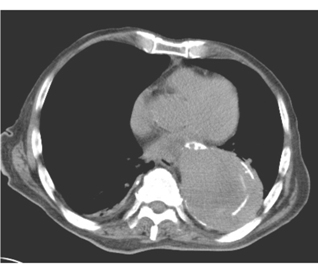

患者,男,45歲。突感胸骨后疼痛來院就診。胸部CT平掃圖像如下圖:

1.本例應診斷為

A.胸主動脈瘤

B.主動脈壁內血腫

C.胸主動脈夾層

D.胸主動脈破裂

E.主動脈炎

2.若要明確診斷可建議進一步做何檢查

A.X線平片

B.胸部超聲

C.MSCTA

D.MRI

E.放射性核素掃描

正確答案:1.C;2.C